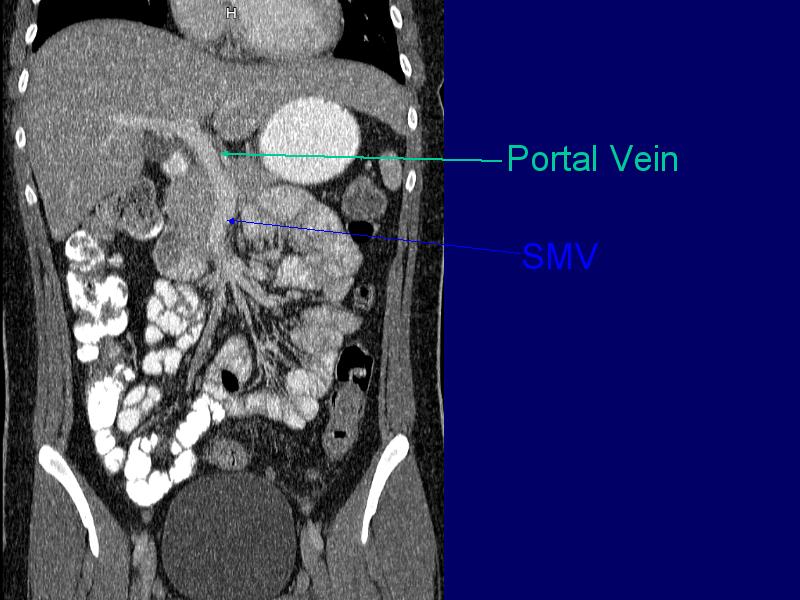

MS 207 SMV